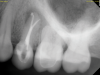

A 52-year-old male patient was seen by his otolaryngologist for symptomatic and unilateral sinusitis of 6 months duration. Medical CT showed dental pathology (Figure 5). His general dentist had a bitewing radiograph on file and referred the patient for endodontic evaluation (Figure 6).

Fig 5. Case 2. Preoperative CT imaging from otolaryngologist showing periapical radiolucency associated with tooth No. 14 and associated maxillary sinus mucositis.

Figure 5